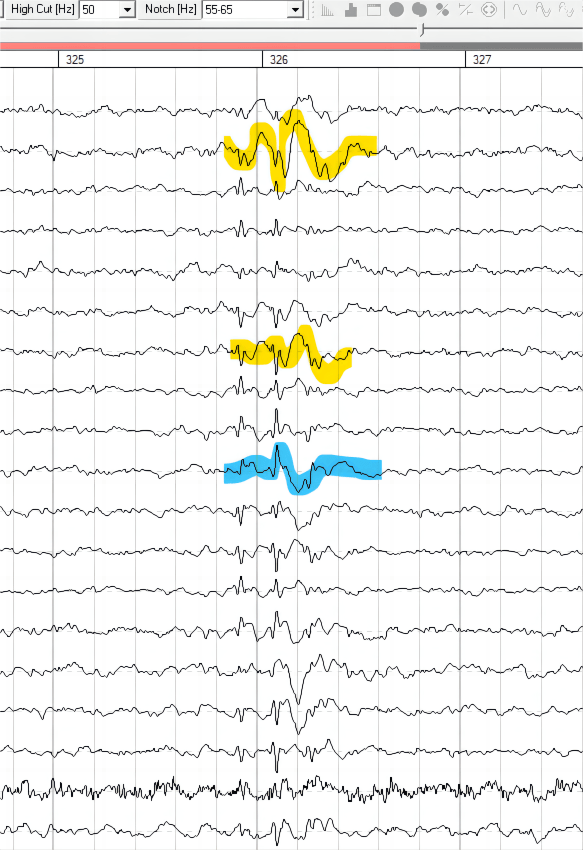

Learn phenotypes, neuro-makers, and raw-data interpretation!

• 3 hours exploring theory, identification, research, treatment, and real data walk-through.

• 3.5 hours exploring theory, training, vigilance considerations, research, and real data walk-through.

• 2.5 hours exploring theory, symptom presentation, training options, research, and real data walk-through.